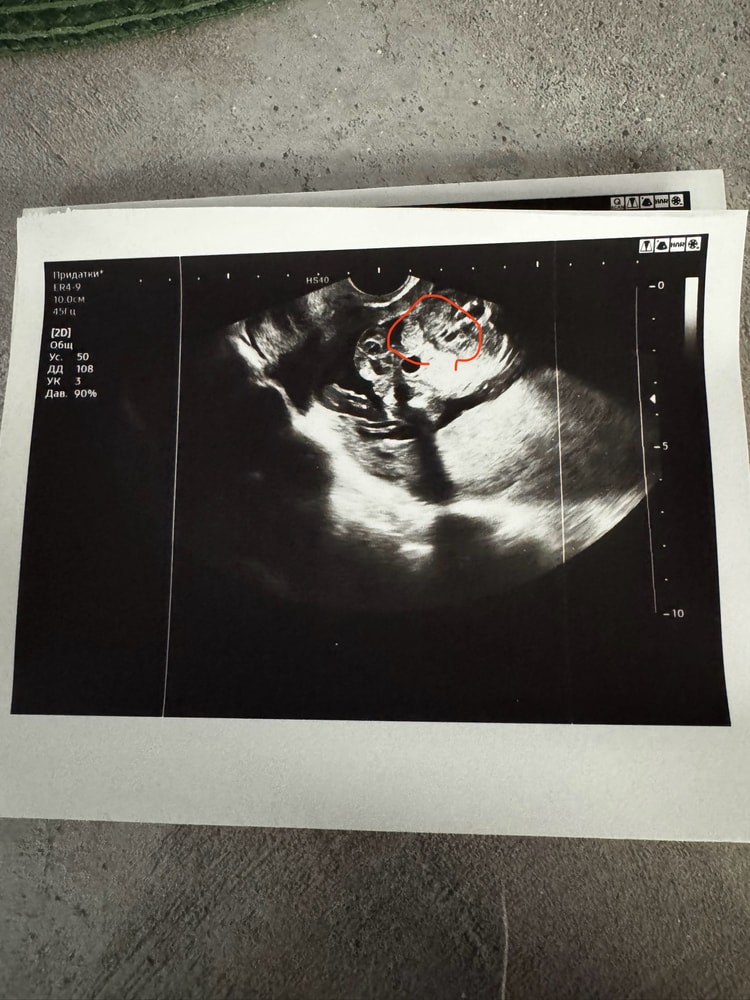

Алина, добрый вечер! А может и мое фото посмотрите😅 ходили на 16й неделе на узи сказали пацан , пришли потом на узи через 2 недели (у мужа день рождения был хотели точно узнать и гендер пати сделать) сказали уже девочка Первое фото 16 недель , второе 18 и вид снизу на пуповине сидит Изображение Изображение

Татьяна, здравствуйте, к сожалению на ваших снимках мне не понятно ничего.

Пол смотрят из позиции вид снизу на попу, как из горшка.

Пирожочек по-другому выглядит, сверху ничего не торчит, а снизу как кофейное зернышко